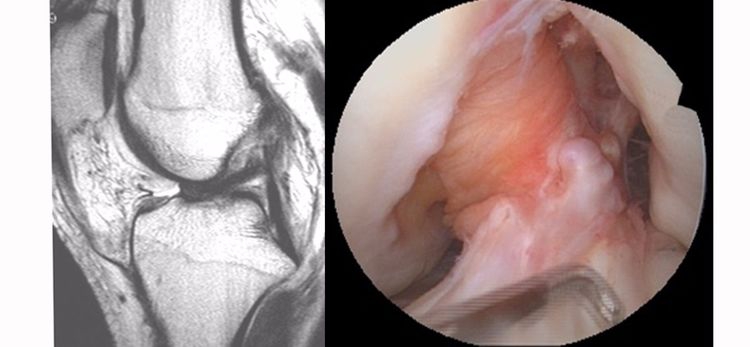

4.Segond骨折:胫骨平台前外侧撕脱骨折(胫骨平台腓骨尖上方,关节线下方的撕脱骨折),多因为下肢过度内翻加内旋暴力所致。骨折本身无特殊治疗。但其强烈提示ACL损伤(75–100%)。

5.前抽屉征:胫骨前移,外侧半月板后角裸露,由于MRI检查时病人为平卧位,胫骨应该因重力而后沉,因此前抽屉征往往暗示膝关节处于交锁状态。

6.ACL出现高信号:ACL信号紊乱,中央夹杂有较多高信号。不一定就是ACL损伤,需要与粘液性变、痛风结晶沉积等鉴别。

7.急性血关节:如果为急性ACL损伤,必然存在着大量的关节内积液(血),否则就不是。

8.胫骨后内侧平台骨折:因为半膜肌的牵拉造成其附着点的撕脱骨折,是ACL损伤中一种比较少见的间接征象。

9.内侧半月板后角撕裂:内侧半月板后角是ACL的重要稳定结构,一旦发现青壮年患者的内侧半月板后角损伤,应该高度怀疑是ACL的继发损伤。常常见于陈旧损伤患者。

10.外侧半月板后根损伤:外侧半月板后根撕裂的受机制与ACL损伤的机制相似,因此发现外侧半月板后根损伤时必须考虑有ACL损伤的可能性。

11.半月板桶柄状撕裂:为膝关节的一种严重损伤,常伴有ACL损伤。

12.内侧副韧带损伤:膝关节损伤三联征=ACL+内侧半月板+内侧副韧带损伤,因此,内侧副韧带的严重损伤应该考虑可能有ACL损伤。

13.后交叉韧带弯曲角度异常:矢状位正常的PCL为凸面向后的弓形,边缘光滑。PCL弯曲角度的异常有可能是ACL损伤所致,但准确性不高。